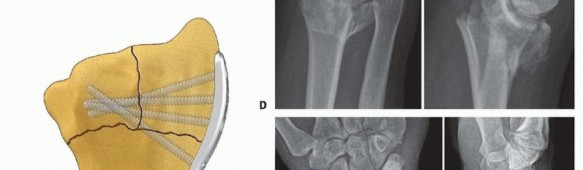

TECH FIG 9 • Radial column fixation with fixed-angle radial column plate. A. Provisional placement of fixed-angle radial column plate. B. Drilling holes for distal fixed-angled pegs. C. Completed fixation. D. Unstable fracture injury films with segmental radial column comminution. E. Films 2 months postoperatively. Fixed-angle radial column support is used to avoid radial column shortening. 88 ## Ulnar Corner and Dorsal Wall Fixation Ulnar Pin Plate Through a dorsal approach, expose and reduce the dorsal ulnar corner fragment, dorsal wall fragment, or both. Insert a 0.045-inch Kirschner wire through the fragment ( TECH FIG 10A), angled proximally and slightly radially to purchase the far cortex of the proximal fragment. Insert structural bone graft into the metaphyseal defect if present to support the subarticular surface. If the plate is aligned along the pulnar border of the shaft, add a 15-degree torsional bend to the plate (twist the proximal end of the plate into slight supination). Often, a little extra extension can be contoured at the distal end of the plate ( TECH FIG 10B).

TECH FIG 10 • Ulnar corner fixation with an ulnar pin plate. A. Insertion of the interfragmentary Kirschner wire. B. Contouring the plate. C. Application of the plate and insertion of the initial fixation screw. D. Fixation completed. E,F. Radial and ulnar pin plate fixation of a three-part articular pattern (radial column and ulnar corner fragment). Slide the plate over the Kirschner wire and fix it proximally with a 2.3-mm bone screw ( TECH FIG 10C). Insert a second Kirschner wire if the fragment is large enough. Create and impact hooks as described for the radial pin plate ( TECH FIG 10D-F). If the Kirschner wire tips protrude beyond the volar cortex, they can be cut flush to the bone surface through a volar incision. Dorsal Buttress Pin Through a dorsal approach, expose and reduce the dorsal ulnar corner fragment, dorsal wall fragment, or both. Insert structural bone graft into the metaphyseal defect if present to support the subarticular surface. Insert two 0.045-inch Kirschner wires through the dorsal cortex and behind the subchondral bone; check the position with 89 the C-arm ( TECH FIG 11A). The Kirschner wires should be separated by about 1 cm and should be transverse to the longitudinal axis of the shaft; on the lateral view, it may be necessary to angle the Kirschner wires proximally to avoid penetration into the joint if the entry site is near the dorsal rim. Initially placing a dorsal buttress pin upside-down on the bone can be helpful as a template in order to visualize the proper position and insertion angle of the Kirschner wires ( TECH FIG 11B). Particular attention should be given to determining whether the insertion angle should include some pronation or supination in order to avoid torsion of the wire form as it is secured proximally.

TECH FIG 11 • Dorsal buttress pin fixation. A. The position of the Kirschner wires is checked with a Carm before inserting the implant. B. Placing an implant upside-down on bone to template the trajectory of the Kirschner wires. C. Inserting the dorsal buttress pin. D. Buttress pin fixation completed. E,F. Fixation of a three-part articular fracture with radial column and ulnar corner fragment with radial column plate and dorsal buttress pin. Ensure that the leading tips of the legs of the dorsal buttress pin are straight and cut to the required length. Leave the ulnar leg 2 to 3 mm longer than the radial leg so one leg can be engaged at a time. Direct the legs proximally if needed to match the insertion angle of the Kirschner wires. Place the ulnar leg of the buttress pin adjacent to the insertion site of the ulnar Kirschner wire, and then withdraw the Kirschner wire and immediately engage the leg in the hole ( TECH FIG 11C). Repeat with the radial Kirschner wire to engage the radial leg of the buttress pin. Impact and seat the buttress pin ( TECH FIG 11D). Fine-tune the reduction and complete the fixation proximally with one or two 2.3-mm cortical bone screws and washers ( TECH FIG 11E,F). If needed, a blocking screw can be placed just proximal to the end of the buttress pin to prevent shortening of the fragment. Dorsal Hook Plate Fixation Dorsal hook plates are another alternative for fixation of dorsal fragments. Expose and reduce ulnar corner and/or dorsal wall fragments according to the technique described previously. Position and insert a 0.045-inch Kirschner guidewire distally along the intended path of the hooks of the plate. Confirm the position with the C-arm. If needed, predrill the holes for insertion of the hooks. In osteoporotic bone, the hooks can be simply pushed into the fragment ( TECH FIG 12A). Verify the position and reduction with C-arm and complete fixation with proximal bone screws ( TECH FIG 12B). 90